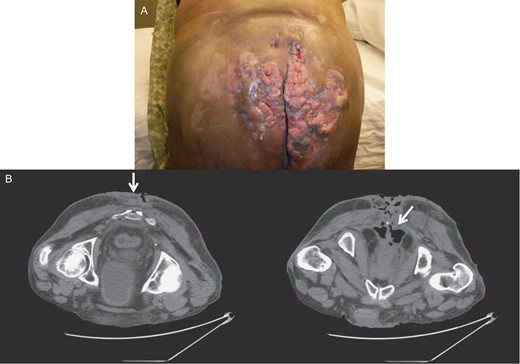

Four months later, after completion of the chemoradiotherapy, there was a significant resolution of the tumor (Fig. 3). No lesions could be felt on the rectal exam. The endoscopy and CT scan after another three months confirmed regression without presence of lesions. The scarred and necrotic soft tissue appeared to be residual from the chemoradiation and was debrided.

Gross image (A) and CT of the pelvis and perineum (B) showing tumor resolution and residual lesions after chemoradiation therapy.